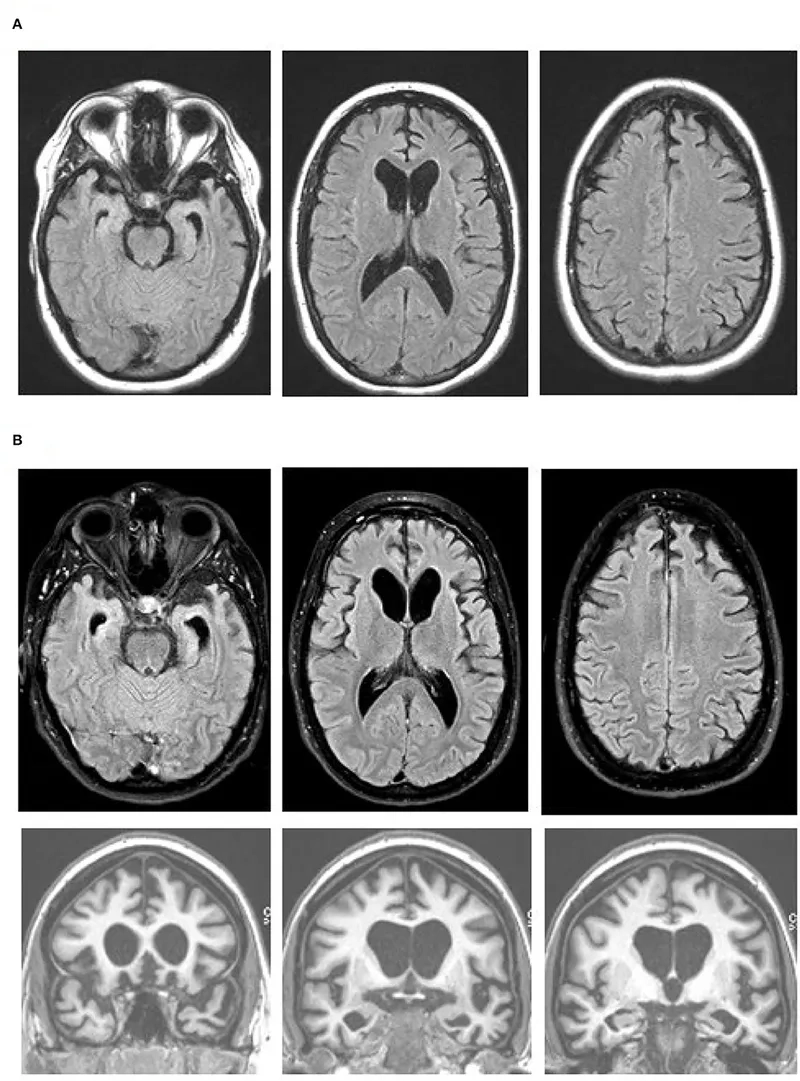

A visual guide to the stages of FTD